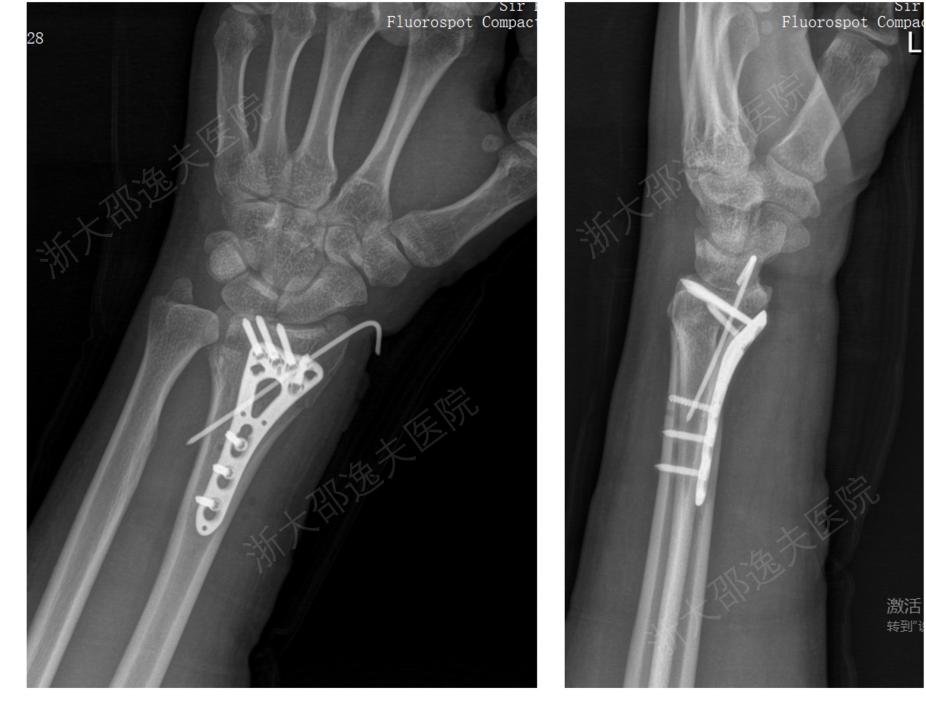

一位年轻工人因外伤导致腕部桡骨远端粉碎性骨折,传统治疗方案需大切口植入钢板螺钉,不仅创伤大、存在肌腱粘连或神经损伤风险,且需术后一年进行二次手术取出。

应用“骨02”黏合技术,团队仅通过一个2—3厘米的微创切口注入“胶水”材料,短短3分钟内即完成了粉碎骨块的精准黏合与固定。术后3个月随访显示,患者骨折愈合良好,无并发症,腕关节功能完全恢复。

△桡骨远端骨折通过“骨02”治疗病例